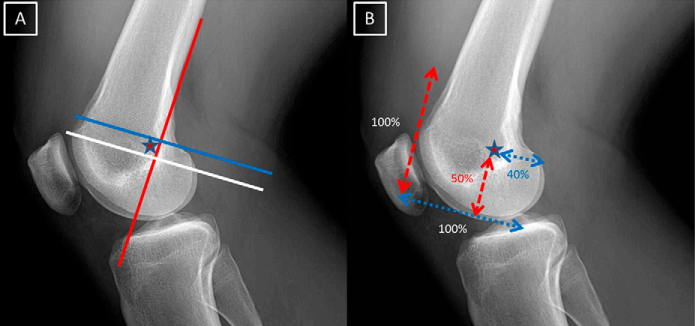

MPFL 股骨侧定位:

内侧髌股韧带(MPFL)股骨端的起源是基于 Schottle 点上,Schottle 点(星)是股骨后方皮质的切线前方 1 mm(红色线),股骨髁上缘垂线远端 2.5 毫米(白色线),和 Blumensaat 线上后方的近端垂直线(蓝线)。

标准尺寸:

当股骨内侧髁被认为是水平距离 100%,髌骨上关节缘至股骨髁远端边界是纵向距离 100%,MPFL 附着点位于股骨内侧髁上距离后方 40%,远端 50%,前方 60% 的位置(星)。